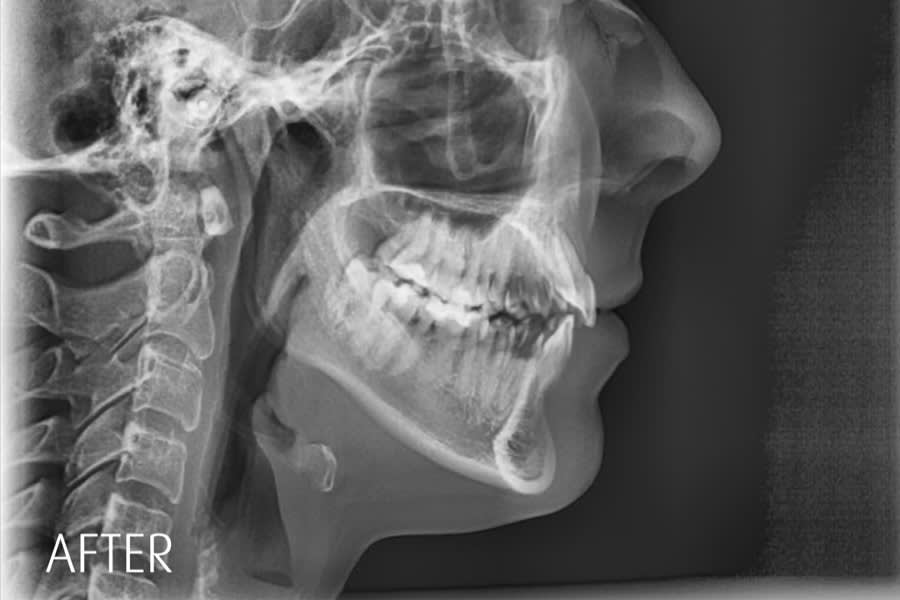

Radiographic Follow-up

Panoramic/cephalometric re-evaluation is used to document posterior intrusion without root resorption or sinus compromise, improved upper incisor angulation in bone, lip profile changes consistent with CCW autorotation, and favorable skeletal parameters.7,17-21 (Figure 18 through Figure 21)